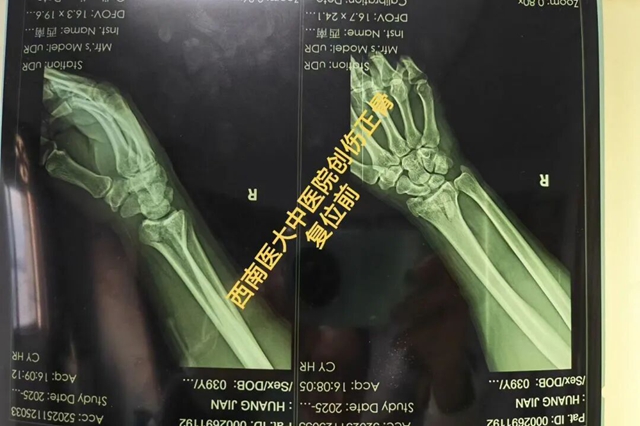

事故发生后,黄先生被紧急送往就近医院就诊。影像检查结果清晰显示:右侧桡骨远端粉碎性骨折。医生当即给出手术治疗的建议,但一想到要开刀、留疤痕,术后还要经历漫长的恢复期,黄先生满是抗拒。

接诊的张小敏主治中医师接过黄先生的检查报告后,细致分析骨折移位情况,又耐心为黄先生进行了详细查体。“关节面粉碎,手法复位有难度,但是我们仍然可以通过牵引的方式恢复关节塌陷,再采用拽、按等手法恢复桡骨高度和关节面平整。” 张小敏用温和的语气瞬间缓解了黄先生的紧张情绪。

随后,复位准备工作有条不紊地展开——皮肤消毒、制备小夹板、调和外敷中药。一切准备就绪后,在同事的配合下张小敏开始为黄先生进行手法复位。

第一步:对右手手腕进行持续纵向牵引;

第二步:待骨折重叠移位逐渐牵引开后,根据骨折移位情况,采用提按端挤、抱迫靠拢、屈伸对合等手法使移位的骨折块重新归位;

第三步:敷上医院特色院内制剂,选用特色小夹板固定;

第四步:采用理筋手法使骨折周围的肌腱等软组织恢复正常位置,最后检查骨折固定的松紧度。

“太神奇了!现在手腕一下子就不那么胀痛了,也能轻微活动了!” 黄先生当场惊喜地说道。后续复查显示,黄先生骨折复位良好,经过一段时间的康复锻炼,黄先生的手腕功能逐渐恢复正常,重返工作岗位。